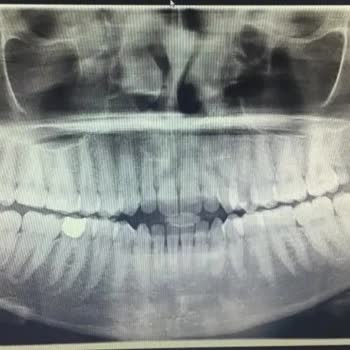

Daha önceki konularımda doktorumdan bahsetmiştim. İzmir'de seyithan kırtay rinoplasti oldum. 1,5 yıl önce. Her şey çok iyi çok güzeldi ta ki burundaki şişler inip durum farkedinceye kadar. Doktorum hep ilgili gibiydi tabi ki şikayetlerimi anlatana kadar. Dişimi yaptırmaya gittiğimde röntgen çektiler ve ilk yamukluğu röntgende fark ettim. Columella yamulmuş sol burun deliğimin üstündeki kıkırdak düşmüş. Fotoğrafı ve bazı şikayetlerimi dile getirince doktorum hiç ilgilenmemeye başladı. Sağ deliğin içinde hep ödem olduğunu düşündüğüm bir şişlik vardı meğer ödem değil et parçasıymış. Bundan dolayı sağ delik kapalı nefes alamıyorum yatarken ve rüzgar gibi ses geliyor. Bir de septum sağa doğru yamulmuş. Bir burun deliğim geniş büyük biri normal. Sağ burun girişinde bir şişlik var hala geçmedi. Ben bunları dile getirmeye başlayınca melake olan doktor bana sürekli görüldü atmaya cevap vermemeye başladı. Üstüne beni bir de engelemiş. Sanki sapasağlam burnumu bu hale ben getirdim.   Hiç şikayet etmeyince iyisiniz ama yaptığı hataları söyleyince sizden kötüsü yok! Bir canla beraber ömür boyu sürecek bir psikolojide teslim ediyorsunuz ama onlar içineedip bırakıyor ve hiçbir şey olmamış gibi hayatlarına devam ediyorlar.